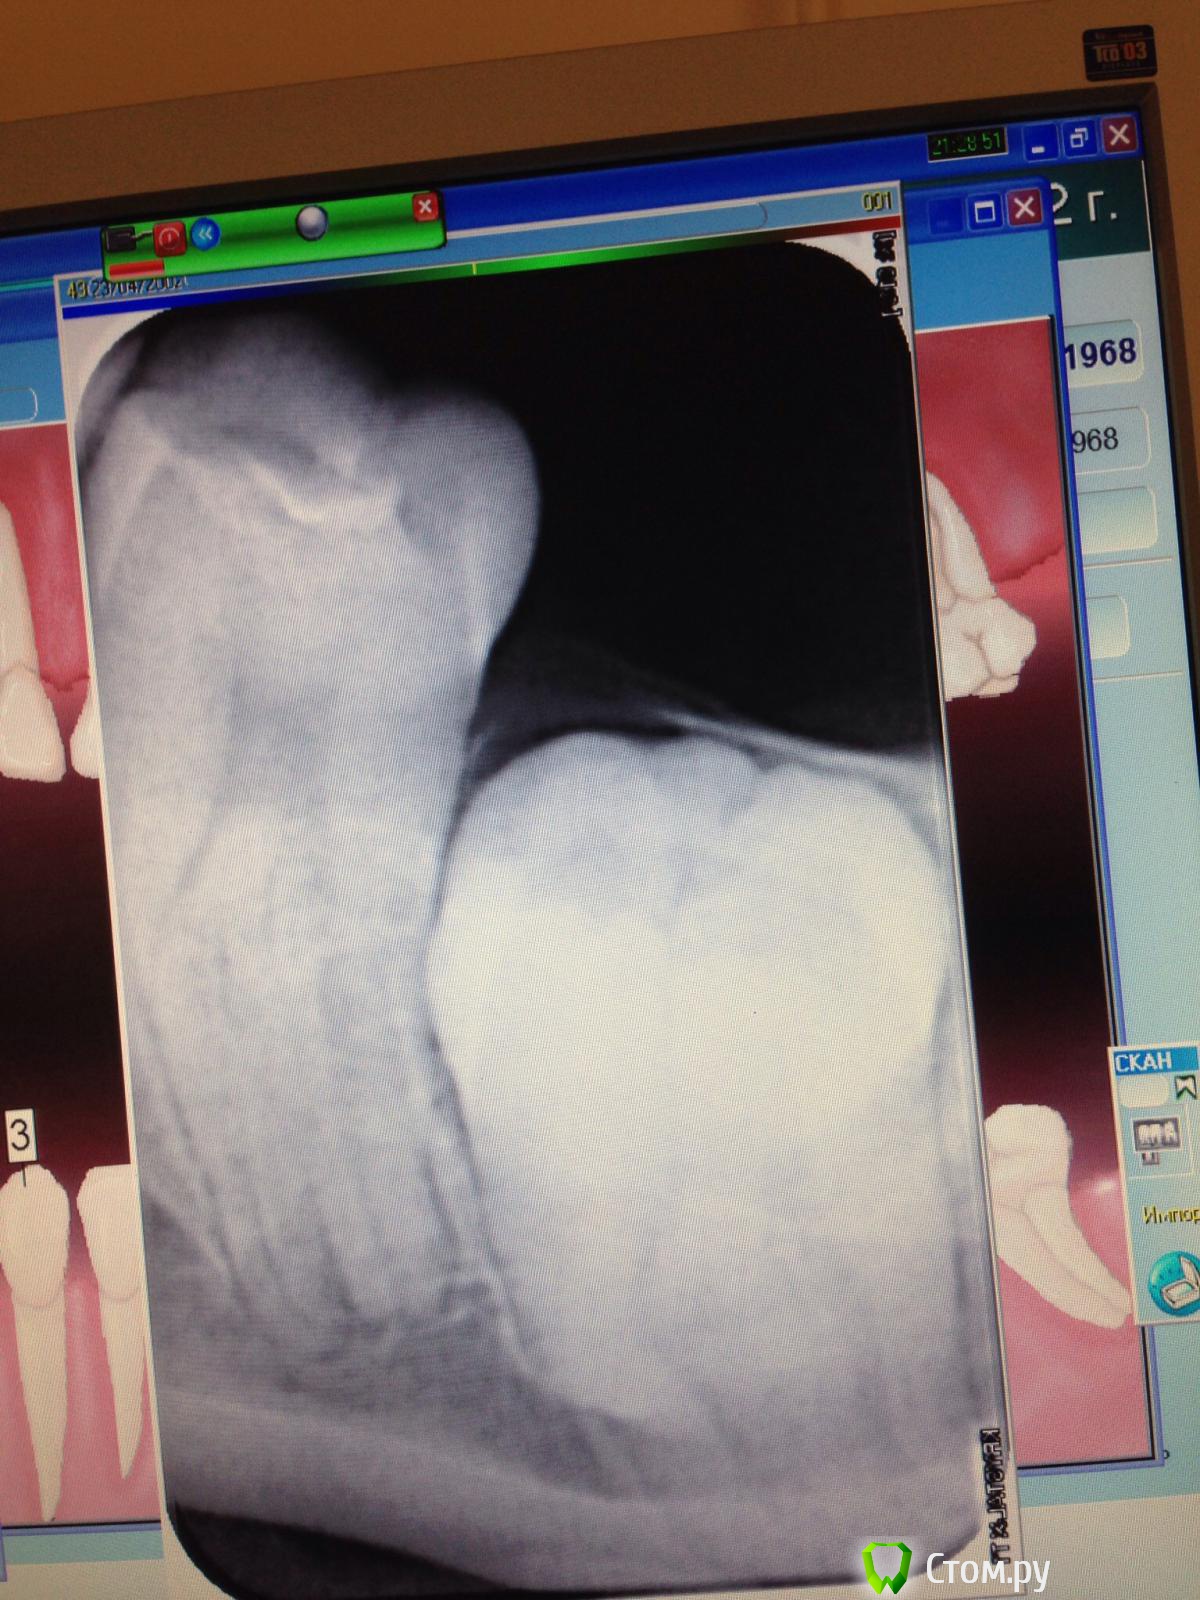

Zuri Опубликовано 17 июля, 2014 Поделиться Опубликовано 17 июля, 2014 (изменено) Здравствуйте, доктора. Пациентка 15 лет. В 47 зубе большая дистальная полость, заросшая десной; перкуссия положительная. Как думаете, лечить или удалить зуб, в надежде, что восьмой прорежется на его место? Если лечить, то чем восстанавливать? Вкв или штифт и билдап? Попробую вставить снимок. Заранее спасибо. Изменено 17 июля, 2014 пользователем Zuri Ссылка на комментарий

Zuri Опубликовано 17 июля, 2014 Автор Поделиться Опубликовано 17 июля, 2014 (изменено) Изменено 17 июля, 2014 пользователем Zuri Ссылка на комментарий

Zuri Опубликовано 17 июля, 2014 Автор Поделиться Опубликовано 17 июля, 2014 Кажись, разобралась ) извиняюсь, впервые создаю пост. Ссылка на комментарий